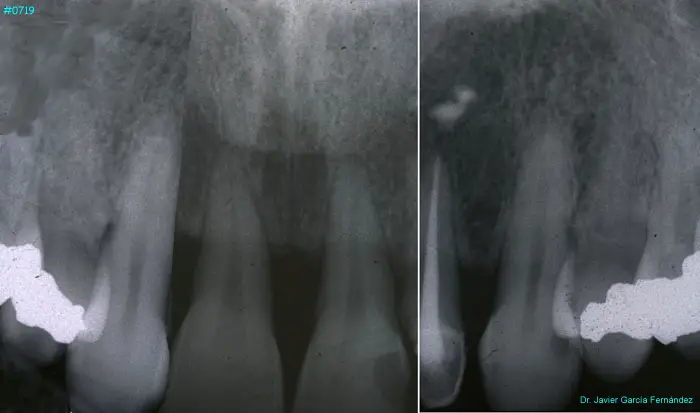

Atlas of Surgical Techniques in Periodontics. Chapter III. Atlas de Técnicas Quirúrgicas en Periodoncia